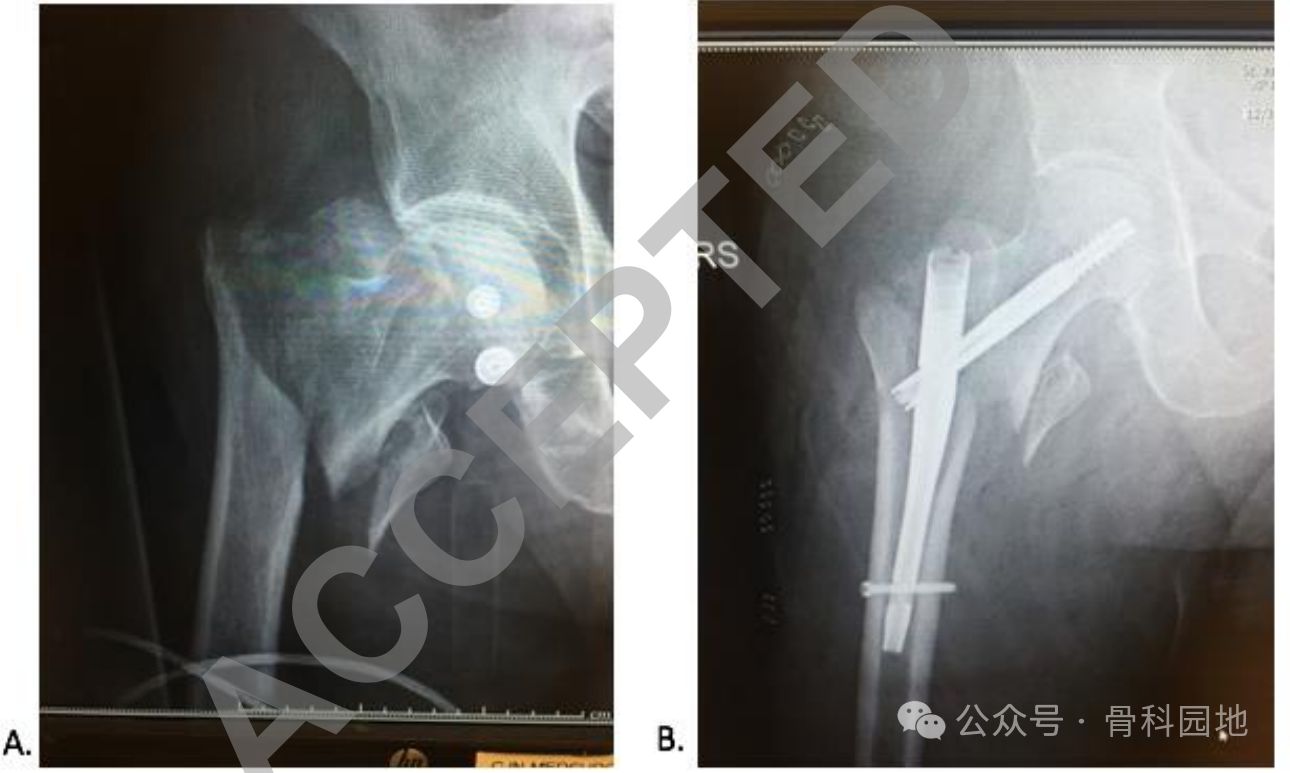

髓内钉已广泛的应用在股骨粗隆间骨折,“楔形畸形”是髓内钉可导致骨折内翻对齐不良。

在最基本的操作是轻柔的使用铰刀减少骨折撑开,或找合适的进针点。在使用锥形铰刀时,如果没有辅助操作,例如巾钳、骨折复位器(如下图),很难避免。

使在正确的夹持位置和小心使用铰刀的情况下,仍可能发生楔形畸形,另一种有用的方法是使用空心钻或环钻来建立起始入口。环钻铰刀是特别有效的,因为它们是中空的,在前进的过程中可以去除一个骨芯。(下图)